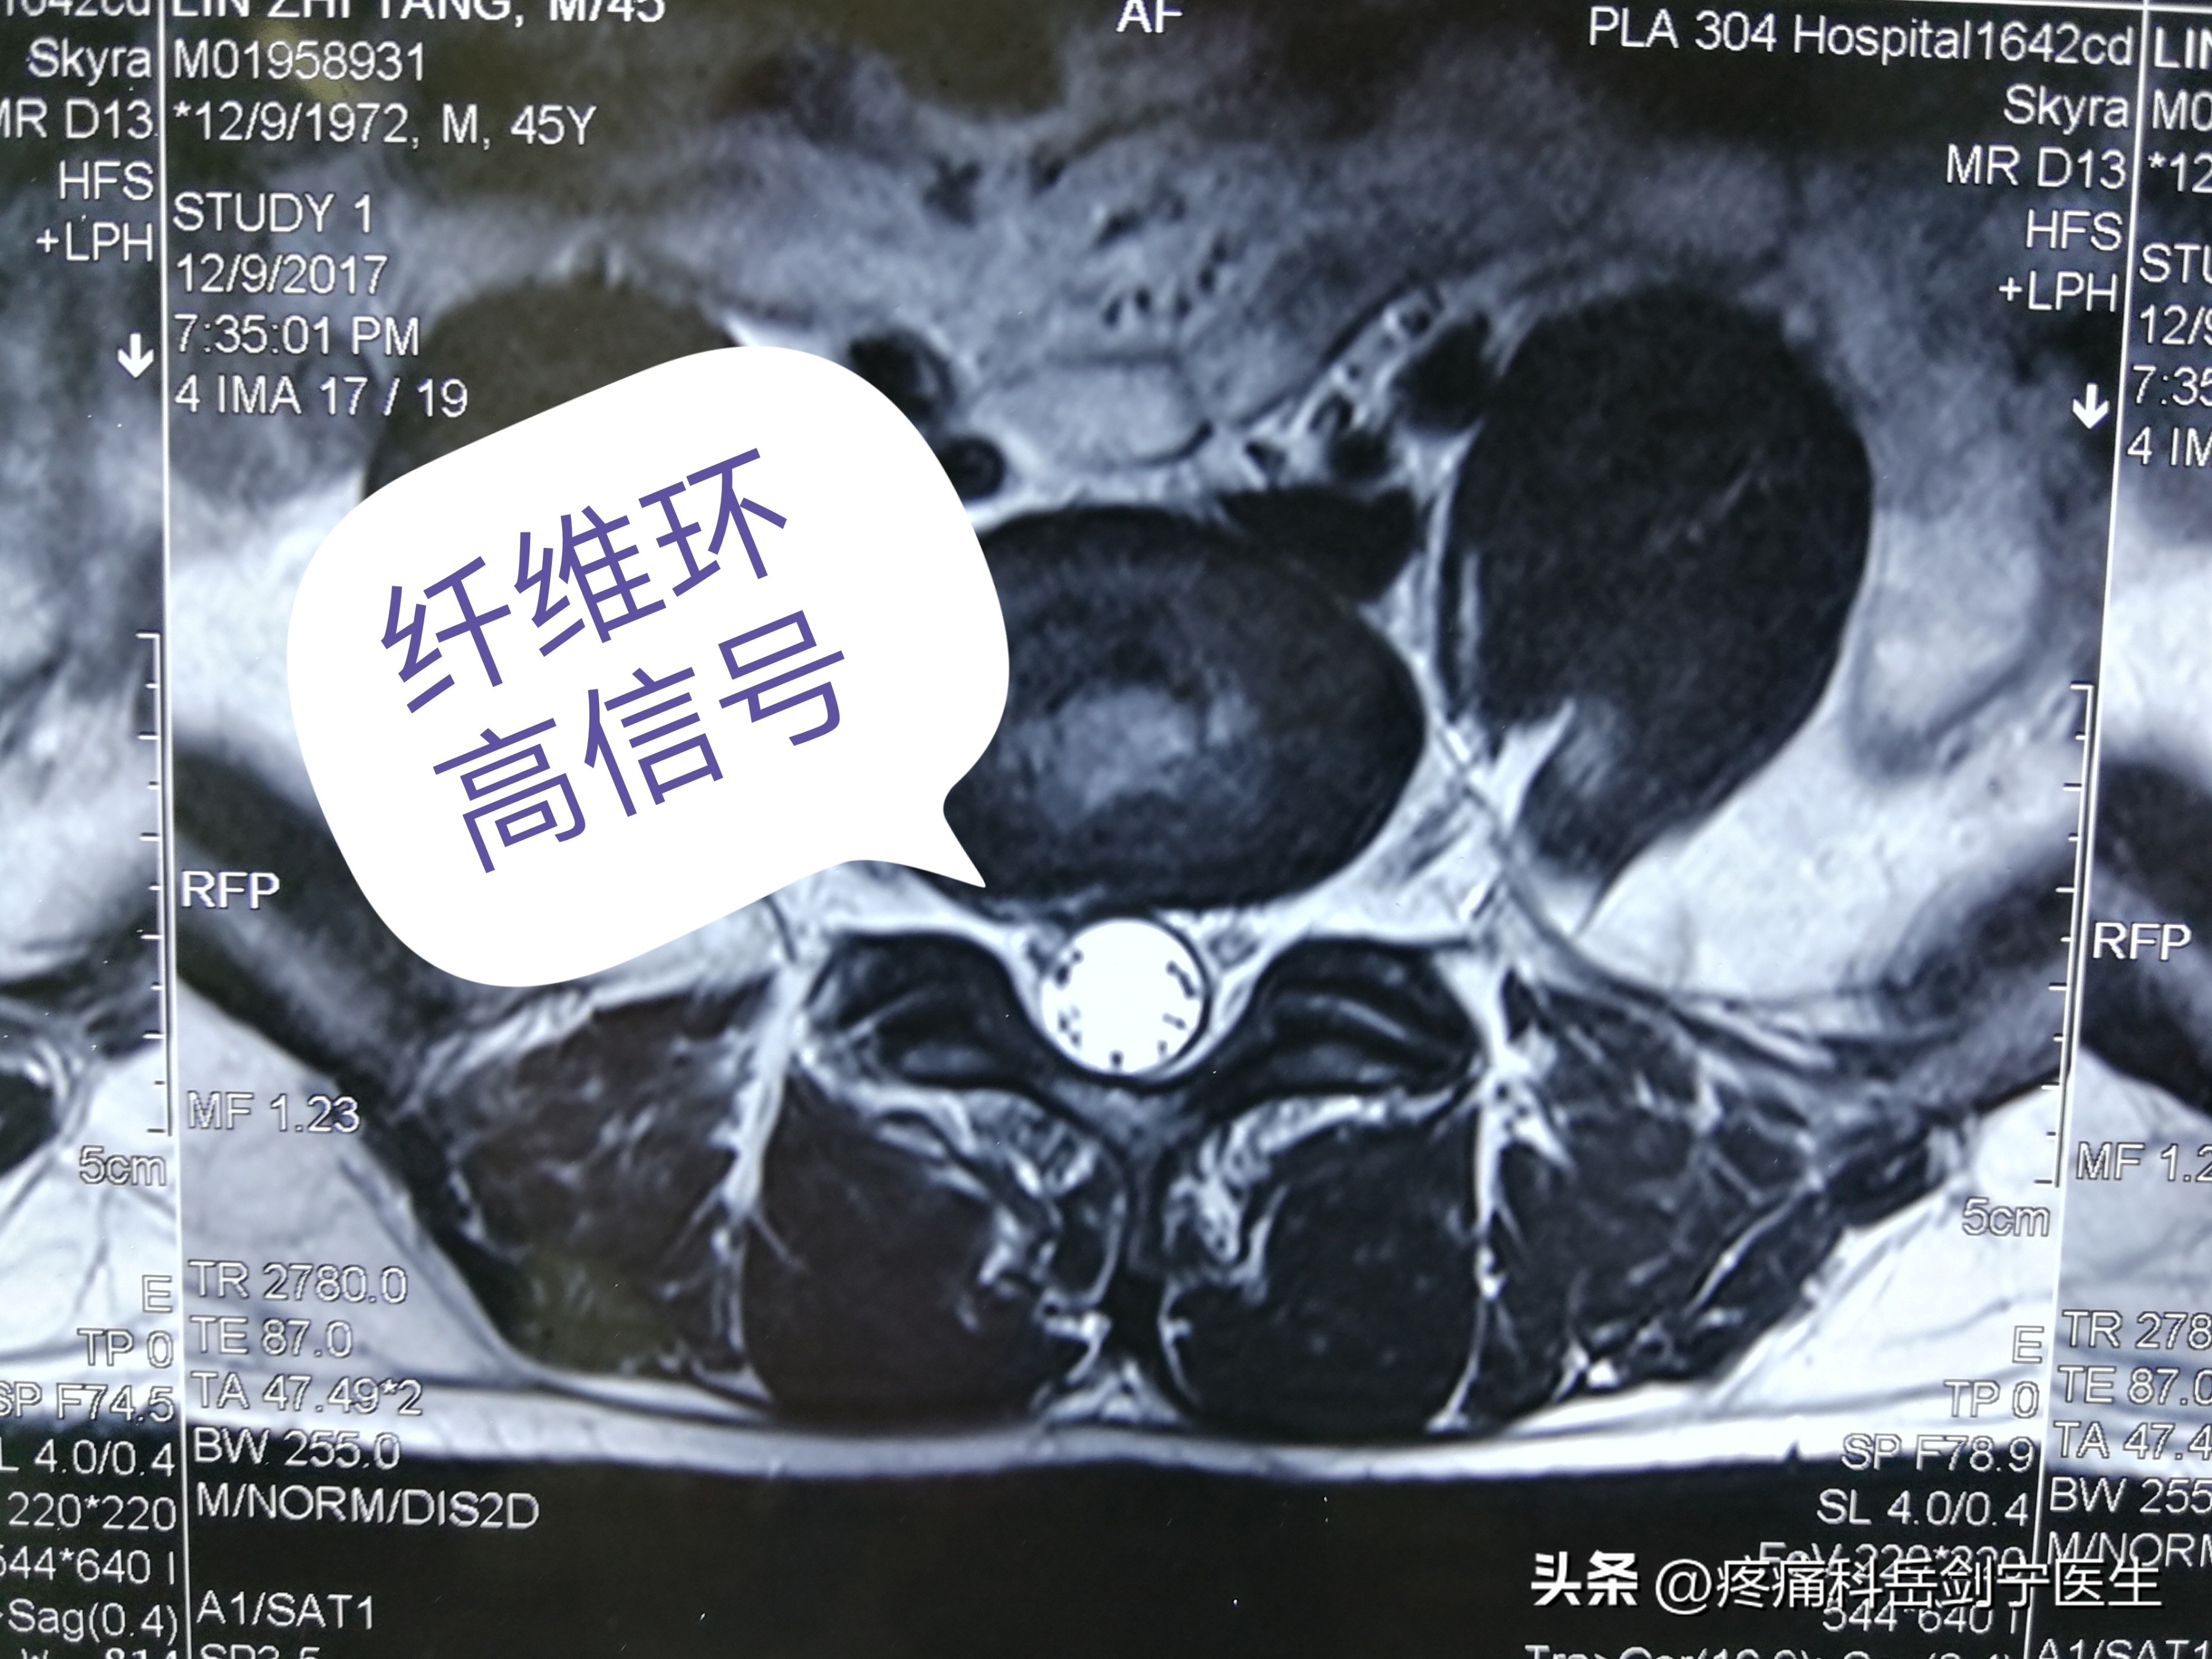

2.核磁:病变纤维环做薄层扫描:矢状位可以看到在后纵韧带的位置,在椎间盘的后缘可以看到高亮信号,提示局部可能会有纤维环破裂。在横轴位可以看到髓核组织向后突出,T1和T2像可见纤维环附近出现环形线状高信号。